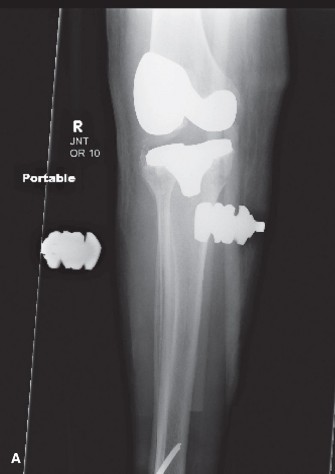

A 72-year-old who underwent a total knee replacement 6 weeks ago, presents with increasing knee pain and swelling, with raised inflammatory markers. An aspiration of the joint cultures coagulase-negative staphylococcus. The next most appropriate step in management is?

Clinical Rationale

Open washout/debridement, polyethylene exchange and intravenous antibiotics. This patient presents with an early prosthetic infection. The accepted treatment is an open debridement and intravenous antibiotics. Arthroscopic washout can be effective in some situations, but intravenous antibiotics alone are not likely to be successful. Single or staged revision is acceptable treatment for an infected joint replacement, but would not be used in the first instance, and is reserved for if the initial treatment fails. 108